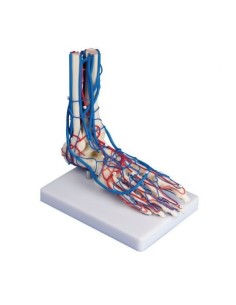

Découvrez le monde de l'anatomie avec des modèles anatomiques de précision

Des modèles anatomiques détaillés pour tous les besoins

Du crâne en 22 parties à verrouillage magnétique aux modèles de colonne vertébrale, des modèles d'articulation aux modèles de cœur, chaque pièce de notre collection est conçue pour une immersion totale dans l'étude de l'anatomie humaine. Nos modèles, réalisés à partir de scans d'os réels, garantissent une expérience tactile authentique et une fidélité de poids presque identique aux originaux.

Indispensables aux étudiants comme aux professionnels, nos modèles anatomiques sont des outils pédagogiques qui permettent d'observer les structures anatomiques avec précision, en évitant les dissections ou les études invasives. Ils sont également utiles pour expliquer les pathologies aux patients, ce qui rend la communication plus efficace et permet de gagner un temps précieux.